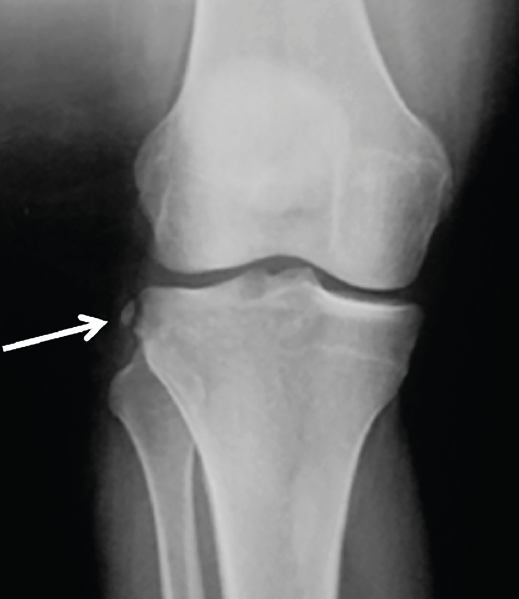

Figura 2. Radiografía anteroposterior de una rodilla derecha, donde puede apreciarse una fractura de Segond (flecha blanca).

- Radiografía (Rx): la imagen radiológica más característica que se relaciona con la lesión del LAL es la fractura de Segond, aunque esta solo está presente en un 1,25% de los pacientes con lesión de LCA(34)(Figura 2).

- Fractura de Segond(48): aunque existe algún trabajo que indica que la fractura de Segond no es un factor de riesgo para la rerrotura de la reconstrucción del LCA(56), los principales grupos aconsejan la reconstrucción del complejo AL cuando esta está presente(42), ya que es sabido que tanto la capa capsuloósea de la banda iliotibial como el LAL(57), así como una expansión de la fascia de la cabeza corta del bíceps femoral(58), están insertados en este punto(41).